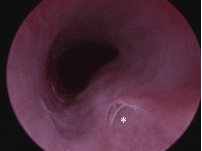

Image of the urethra of female dog with an ectopic ureter using the cystoscope. The ectopic ureter can be seen opening into the urethra (*).

Cystoscopy allows us to see inside the urethra and bladder and identify any problems. This can be useful for diagnosing a variety of issues, including tumours and stones. We use cystoscopy in the diagnosis and treatment of ectopic ureters.

The ureter connects the kidney to the bladder, allowing urine to flow and the bladder to fill. Dogs with an ectopic ureter are born with their ureter in the wrong position. Instead of joining and opening into the bladder, the ureter runs through the wall of the bladder and opens into the urethra. This means that the urine ‘bypasses’ the bladder and this results in it dribbling out (incontinence).